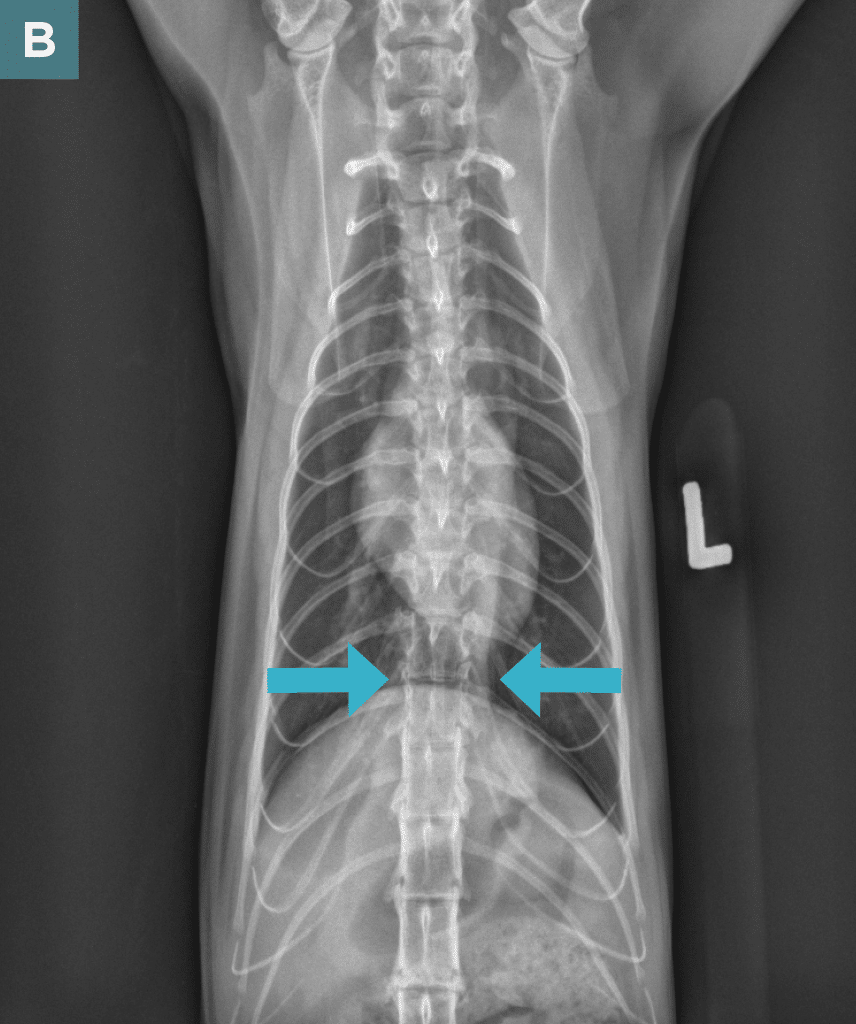

Diagnostic Imaging

On survey thoracic radiographs, the heart and lungs were normal. A soft tissue opacity in broad-based contact with the diaphragm was noted in the caudal thorax (FIGURE 2), and the intra-abdominal portion of the stomach was shifted slightly cranially and to the left; findings were consistent with a hiatal hernia. The cat was anesthetized for computed tomography (CT) of the head and possible surgery.